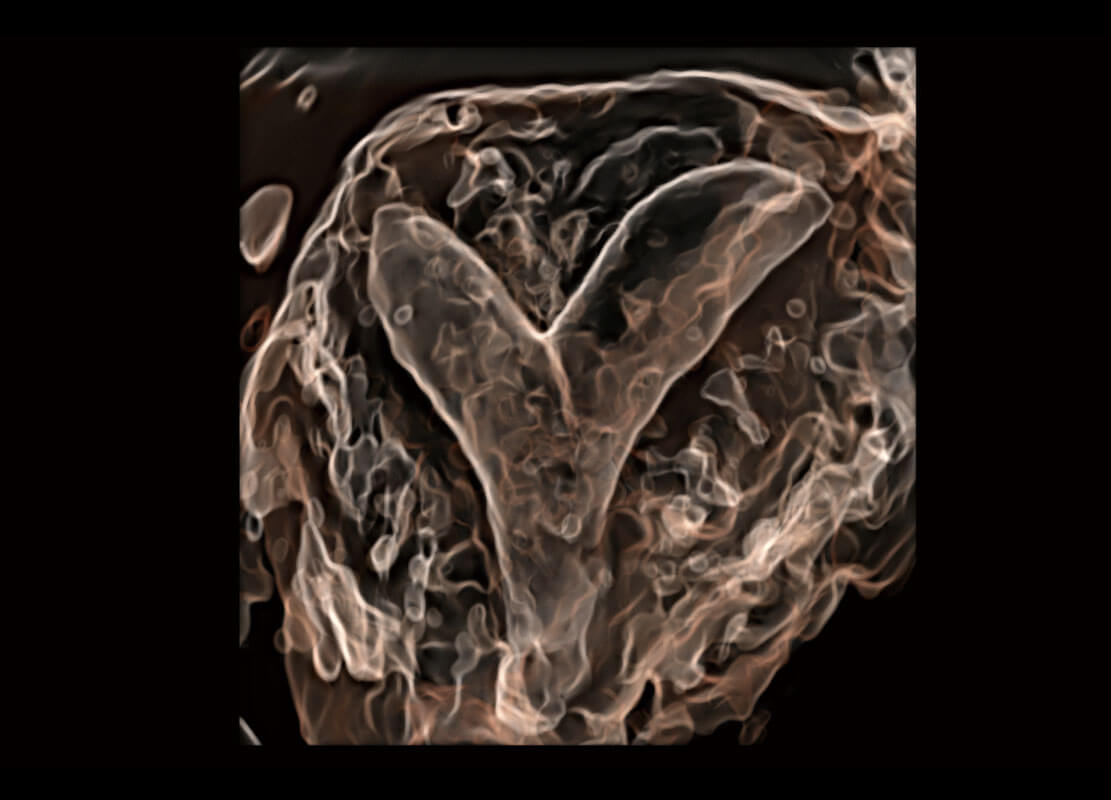

• 腔内三维-宫内节育器

• 腔内三维-光影成像

盆底超声

P60为盆底超声检查提供应用方案,多种腔内及腹部容积探头提供从二维、三维到四维的优异图像品质,实时快速三维容积数据获取,专业的测量工具包等人性化设计,为超声医生诊断提供有力保障。